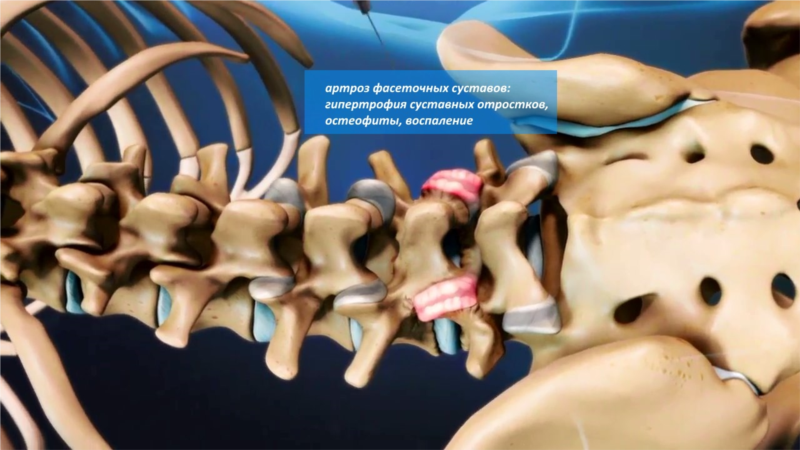

Остеоартрит фасеточных суставов: медицинские снимки и схемы